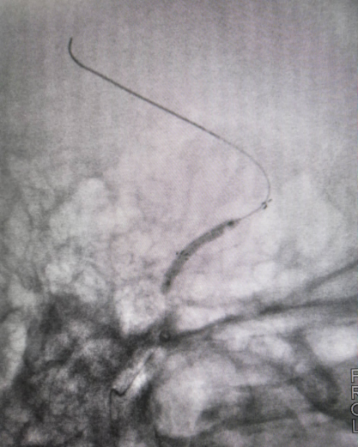

微导丝较顺利通过支架

微导管到位撤出微导丝

Transand微导丝到位撤出微导管